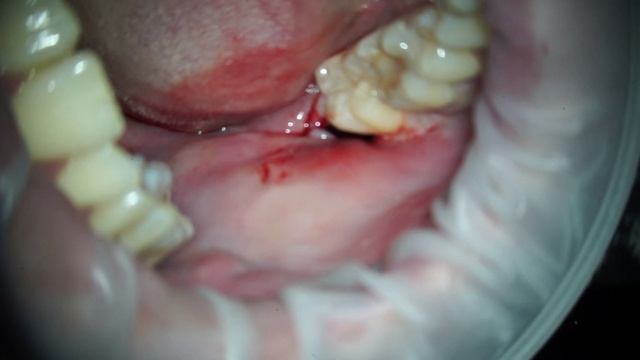

Удаление зуба мудрости смотреть онлайн

01:09

Удаление зуба мудрости

Магический путь 1639 просмотров